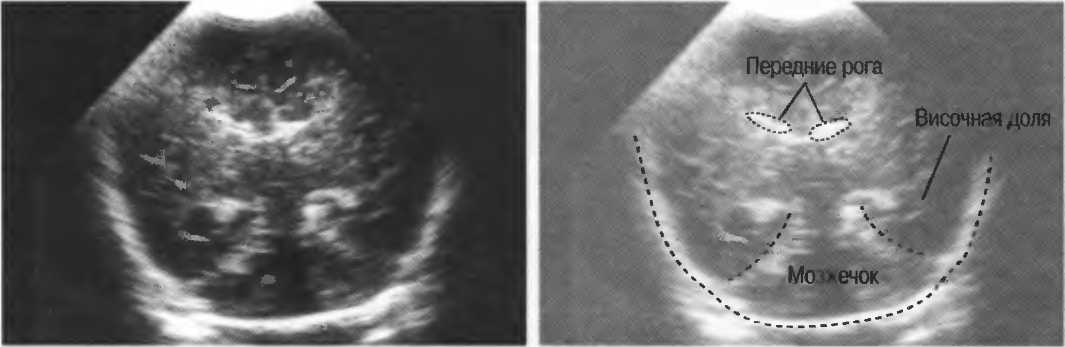

3. Ультразвуковые исследования в педиатрии. Для детей необходим датчик с частотой 5 МГц с глубиной фокусировки на 5-7 см. При исследовании мозга новорожденного используется секторный датчик с частотой 7,5 МГц с глубиной фокусировки на 4-5 см (этот датчик также используется для исследования яичек и структур шеи у взрослых).